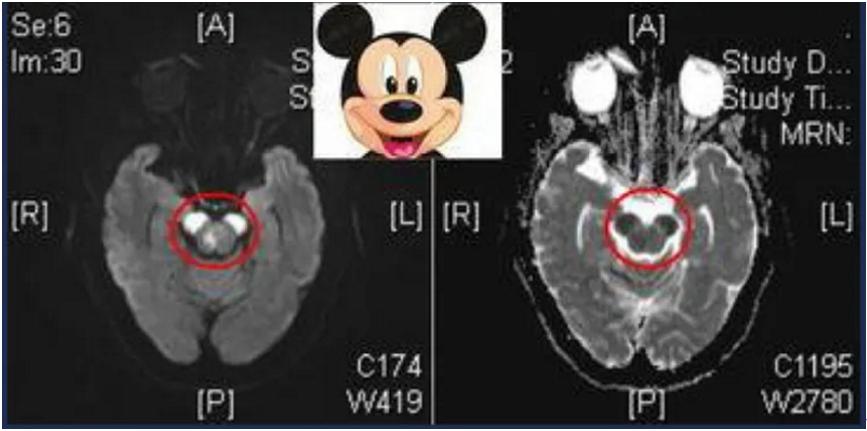

若双侧大脑脚梗死,MRI可见“米老鼠耳朵征”,系双侧皮质脑干束/皮质核束受损:双侧面瘫、舌、咽及构音、吞咽运动均有障碍,不能说话 (完全性假性球麻痹) 及双侧皮质脊髓束受损:四肢瘫、双侧病理征。